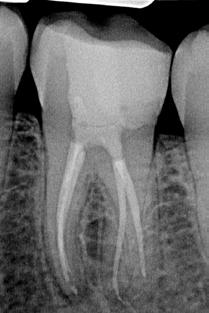

The diagnostic radiograph taken preoperatively shows an insufficient amalgam filling in the distal proximal space. The mesial root shows periapical osteolysis (figure 1).

Electrometric determination of the canal length using a Morita Root ZX Mini Apex Locator was performed with C-Pilots size 8-10. After the working length was determined, the glide path was rotationally extended with EdgeFile X7 size 17.04 and 25.04 and finally prepared to 30.04 (Figure 2).